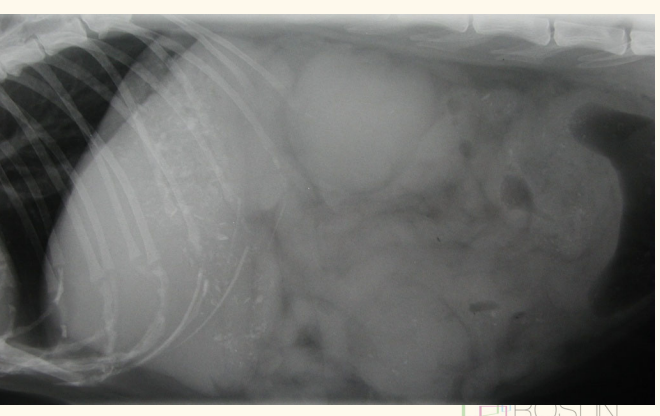

picture: